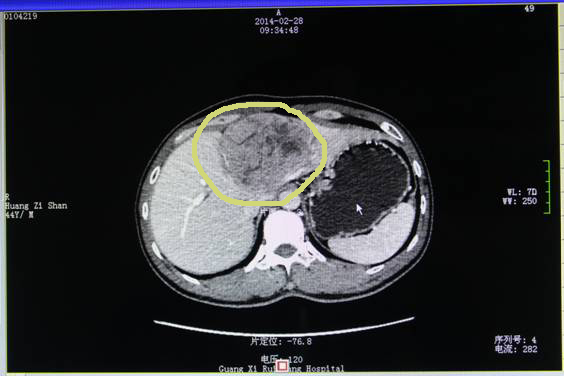

2014年2月27日黄先生来到广西中医药大学附属瑞康医院肿瘤科二区就诊,第二天进行CT检查,发现肝左叶肿块,2月28日行彩超引导下肝肿物穿刺活检术,3月3日病理报告为:中分化肝细胞癌。诊断明确为原发性肝癌。

治疗前肝癌大小